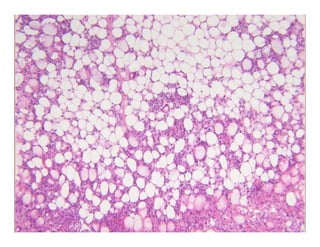

Subcutaneous fat necrosis of theSubcutaneous fat necrosis of the

bbnewbornnewborn

Normal epidermis and dermis with anNormal epidermis and dermis with anNormal epidermis and dermis with anNormal epidermis and dermis with an

underlying lobular panniculitisunderlying lobular panniculitis

–– Mixed inflammatory infiltrateMixed inflammatory infiltrateyy

Many fat cells retain their outlineMany fat cells retain their outline

–– Narrow clefts radiate from periphery of cellNarrow clefts radiate from periphery of cellNarrow clefts radiate from periphery of cellNarrow clefts radiate from periphery of cell

Contain doubly refractile needleContain doubly refractile needle--like crystalslike crystals

Same histology as Sclerema neonatorumSame histology as Sclerema neonatorum

–– Except, SN has less inflammationExcept, SN has less inflammation